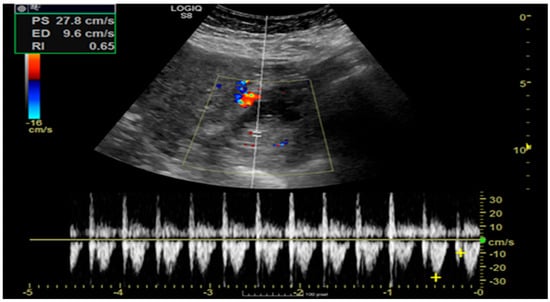

Pregnancy (HP), defined as the coexistence of intrauterine and ectopic gestations, is a rare condition, especially in spontaneous conception, but it is a life-threatening obstetric emergency when rupture occurs, with a reported maternal mortality rate of 0.03%. Diagnosis is often delayed because confirmation of an intrauterine pregnancy can mask clinical signs of a concurrent ectopic gestation. Early recognition and prompt surgical intervention are therefore critical to maternal safety and preservation of intrauterine viability. This case highlights the diagnostic challenges and successful management of a spontaneous ruptured heterotopic pregnancy. Case presentation: A 34-year-old Middle Eastern woman, gravida 4, with a spontaneous conception, presented with sudden severe lower abdominal pain and signs of acute hemoperitoneum (hypotension, tachycardia, and marked peritoneal signs). Transvaginal ultrasound demonstrated a viable intrauterine pregnancy at 9 weeks 4 days gestation, together with a ruptured left tubal ectopic pregnancy of similar gestational age. The patient underwent urgent laparoscopic left salpingectomy with evacuation of approximately 1200 mL of intraperitoneal blood and clots. Postoperatively, she developed significant anemia (hemoglobin drop from 11.2 g/dL on admission to 6.5 g/dL) requiring transfusion of four units of packed red blood cells. Serial ultrasonographic follow-up confirmed ongoing viability of the intrauterine pregnancy, which ultimately resulted in a live birth at term. Progressive resolution of the postoperative pelvic hematoma was also noted. Conclusions: Ruptured heterotopic pregnancy remains a diagnostic and therapeutic challenge. This case, along with a synthesis of the contemporary literature, demonstrates that a high clinical index of suspicion, timely ultrasound diagnosis, and immediate minimally invasive surgical management are paramount. Furthermore, rigorous postoperative monitoring and resuscitation, including targeted transfusion, are essential to achieve maternal stabilization while allowing continuation of a viable intrauterine pregnancy, with reported live birth rates exceeding 70% following timely intervention. Full article